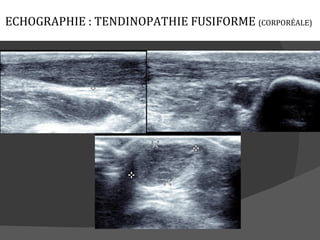

ECHOGRAPHIE : TENDINOPATHIE FUSIFORME (CORPORÉALE)

Tendinopathie (fusiforme, nodules, fente, bursite)

Normal                      Fusiforme